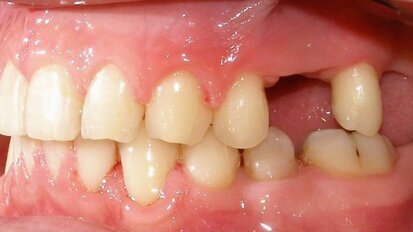

Dva dana ranije, u saobraćajnoj nezgodi, malu Marlenu udario je automobil. Na desnom gornjem centralnom sekutiću bila je prisutna fraktura gleđi i ...